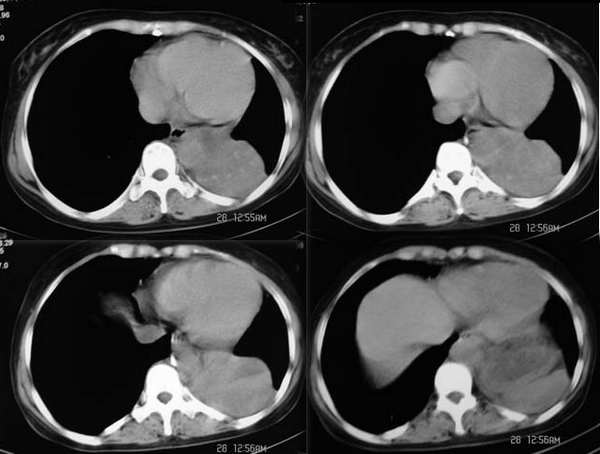

左侧胸廓容积缩小,纵隔左移,左下肺支气管闭塞.考虑中心型肺癌并左肺下叶不张,建议纤支镜.

属典型的左下肺中央型肺癌——左下分叶状肺肿块、支气管阻断、左下肺不张,纵隔淋巴结肿大。

左侧肺部体积缩小,纵隔向患侧偏移,左下肺支气管阻塞,中央型肺癌合并肺不张可能性大。

考虑中心型肺癌并左肺下叶不张

左下叶支气管变窄消失,考虑左侧中心型肺癌伴纵隔淋巴结增大